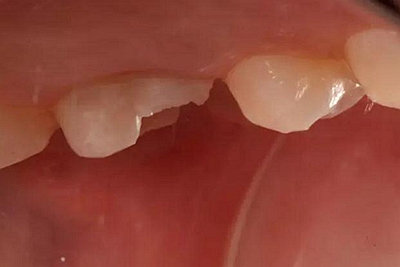

患者女性,55歲,3年前B3纖維樁+鑄瓷全冠修復,一周前牙冠折斷,就診后,發(fā)現(xiàn)纖維樁根管口處折斷,周圍牙齦增生,建議患者行冠延長手術。首先去除斷端的纖維樁。拍片示牙根長度充足。于是開始冠延長手術。

因為是前牙,故該患者將來修復體邊緣必須為齦下,所以3個月后再行修復。以下為手術前照片。

以下為術中照片。

內(nèi)斜切口,頸圈組織,改良垂直褥式縫合。